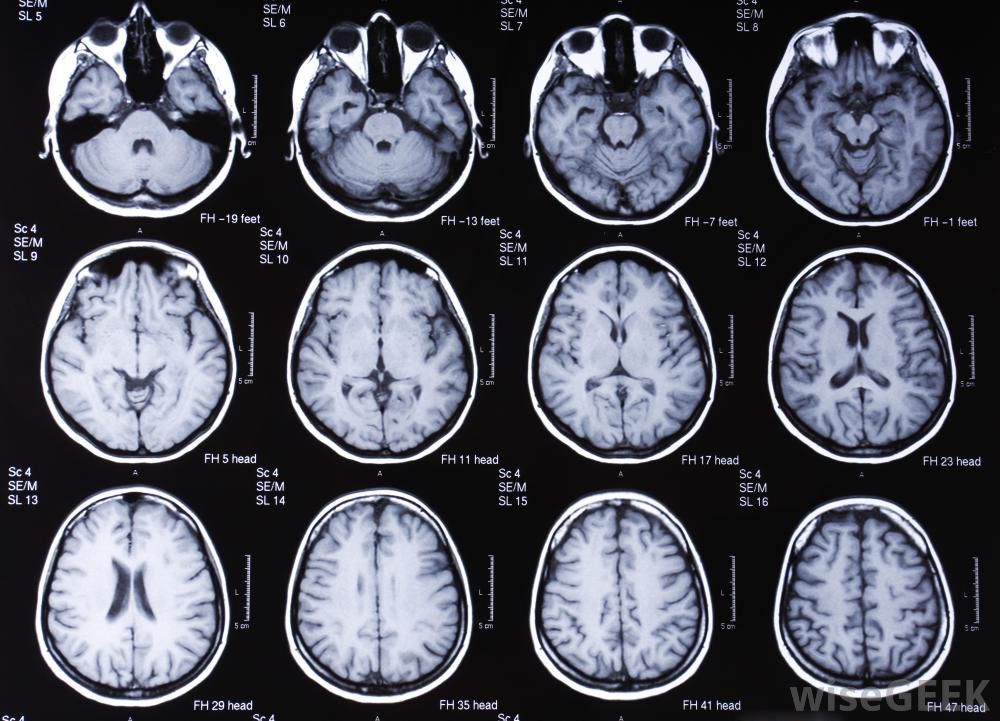

人类脑部的核磁共振图,图来自wiseGEEK

研究者共得到了11只转基因猴。通过核磁共振脑影像分析发现,MCPH1转基因猴的脑子并不会变大。但转基因猴的脑部发育表现出和人脑相似的滞后性特征。人脑的这种滞后性表现为脑部神经发育随着年龄增长缓慢形成,这是人类和非人类灵长类动物的一个关键区别。